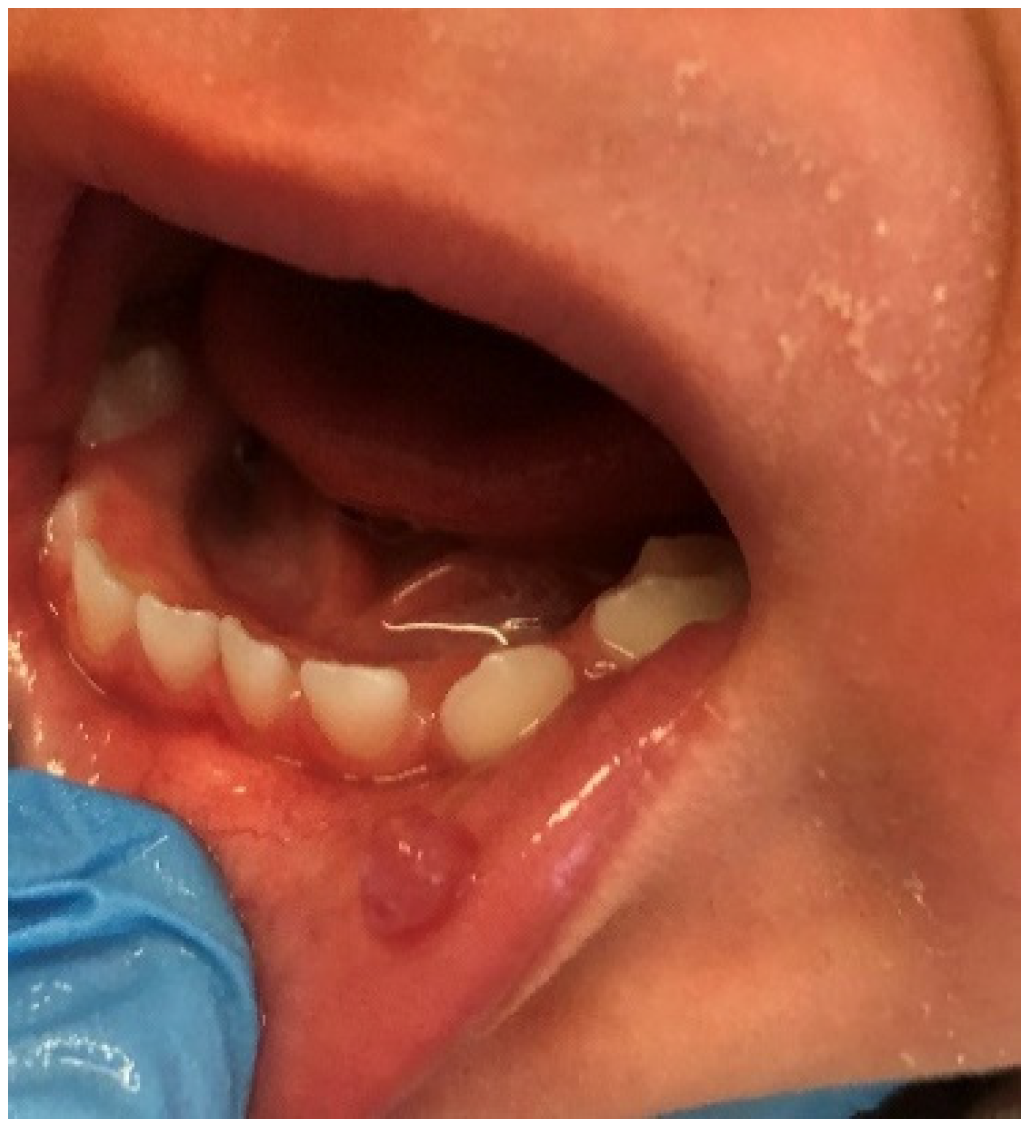

The incidence of pyogenic granuloma—4.2% (Figure 10)—was similar compared to the research carried out by Skinner et al. (4.1%) on 1525 patients aged 1–19 years [38]. This value was also close to the pooled global frequency (4.87%) presented in the most recent review, but lower than the European prevalence (8.82%) of this mucosal alteration revealed in the same article [1]. On the one hand, studies from the UK and Spain even showed a lower frequency than our figure or the European average, 3.06% and 2.2%, respectively [33,39]. On the other hand, Gultelkin et al., in her Turkey-based study, diagnosed pyogenic granuloma in 7% of all of her patients, and Sklavounou-Andrikopoulou et al. reported its incidence in a very high level of 35.1% in the Greek pediatric population [36,40]. In our study, children aged 7–13 and females were more frequently affected (the 5th most common diagnosis among girls, and 3rd among school-age children), which was also reflected in the previous findings [32,33,36,38].

Figure 10.

Pyogenic granuloma around 74 and 75 deciduous teeth in a school-aged female. In this case, pyogenic granuloma appears as a smooth, sessile mass with pink-reddish surface. Typically, the mass is painless and bleeds easily. Gingival irritation and inflammation due to poor oral hygiene—similar to this patient—may be a precipitating factor.